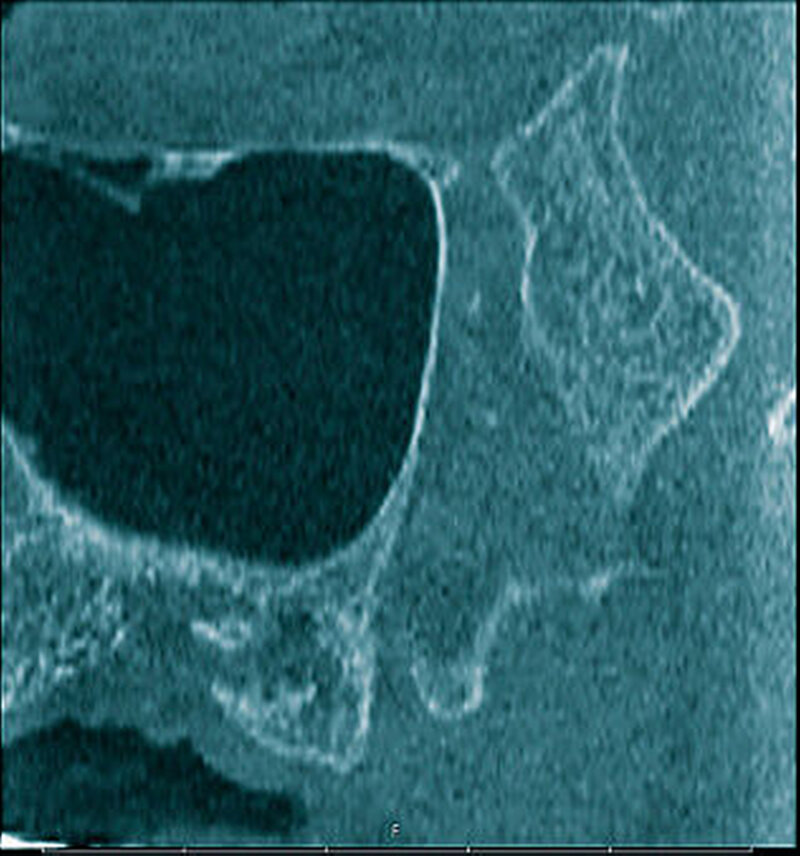

In der digitalen Volumentomografie fiel ein osteolytischer Prozess in der Oberkiefermolarenregion links auf, wobei die bukkale Kompakta weitstreckig unterbrochen war bei noch intakter lateraler und basaler Kieferhöhlenbegrenzung. In einzelnen Schichten tunnelierten die osteolytischen Bereiche die Kompakta (Abbildung 3).

Radiologisch stellen sich braune Tumore als Osteolysen dar, wobei der Knochen bei entsprechender Größe des Befunds auftreiben kann. Häufig zu erkennen ist eine Auflockerung und Rarefizierung der Spongiosa. Die Kompakta kann ausgedünnt sein beziehungsweise völlig fehlen, wobei es häufig zu Tunnelierungen kommt. Das bedeutet, dass die Spongiosa radiologisch stärker affektiert erscheint als die darüber befindliche Kompakta [Freyschmidt, Ostertag et al., 2010].